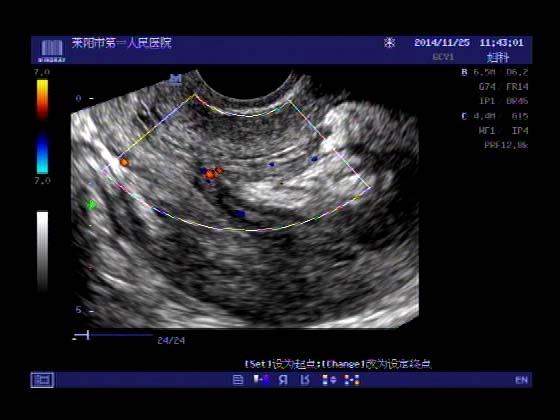

超声入门贴379---------粘膜下肌瘤(阴超的魅力)

女,43岁,月经量多3个多月,加重一个月

外院彩超检查提示:子宫后肌壁略高回声团------肌瘤?息肉?,盆腔少量积液

今天来我院检查:

巧妇难为无米之炊,经腹部超声确实很难定,阴超一目了然,乡镇医院诊断水平的提高更迫切的需要高档仪器的引进!